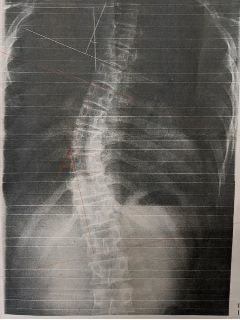

施術19回:コブ角33度

施術前:コブ角40度